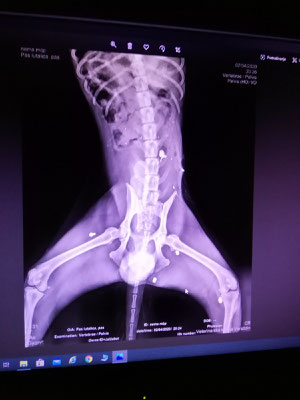

Die Ärzte fanden mehrere Projektile in seinem Körper, das größte im hinteren Bereich der Wirbelsäule. Dieses wurde nach Stabilisierung durch schmerz- und entzündungshemmende Mittel in einer OP entfernt. Bei einem späteren, weiteren Eingriff sollten die restlichen Kugeln herausoperiert werden. Dafür musste Mak aber erstmal wieder zu Kräften kommen. Die Vermutung, dass Mak sehr wahrscheinlich invalide bleiben würde, lag sehr nah, da er nach der Entlassung aus der Klinik nicht stehen konnte.

In seiner Pflegestelle in Deutschland wurde sich dann seit Mitte Oktober letzten Jahres liebevoll um ihn gekümmert und mit physiotherapeutischen Übungen am Muskelaufbau gearbeitet. Bei seiner jetzigen neurologischen Untersuchung zeigte sich eine leichte Arthrose-Entstehung an den Vorderbeinen, die jedoch noch keine Probleme macht. Es wird jetzt angedacht, ihm auf jeden Fall einen angepassten Rolli zur muskulären Entlastung im vorderen und hinteren Bereich zur Seite zu stellen. Die Wirbelsäule ist stabil, durch die Benutzung des Rollwagens können sich keine Splitter an der Wirbelsäule verschieben und das Rückenmark schädigen. Zusätzlich soll Kitai weiterhin Physiotherapie bekommen, so dass die hinteren Beine weiter an Stärke gewinnen und ihm mehr Kraft verleihen.

Aufgrund einer zystischen Systembildung an der Prostata soll Kitai demnächst kastriert werden.